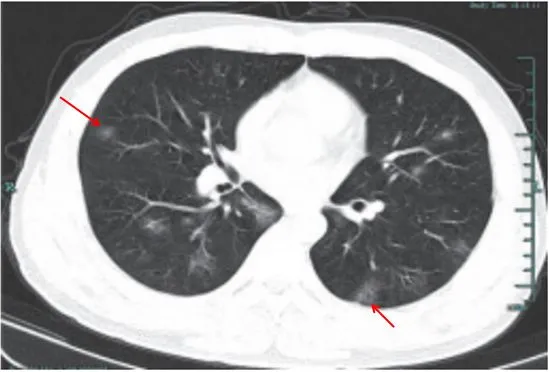

病灶形态以三种类型为主,即多叶多灶分布病灶(图 2-2A) 、单叶片状病灶(图 2-2B)和孤立性类圆形病灶(图 2-2C)

多叶多灶分布病灶(图 2-2A)

单叶片状病灶(图 2-2B)

孤立性类圆形病灶(图 2-2C)